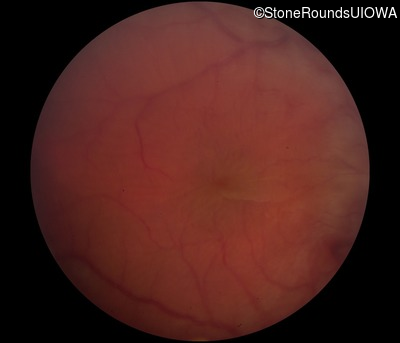

Fundus Photography - Right - 20/300 sc

Exemplar